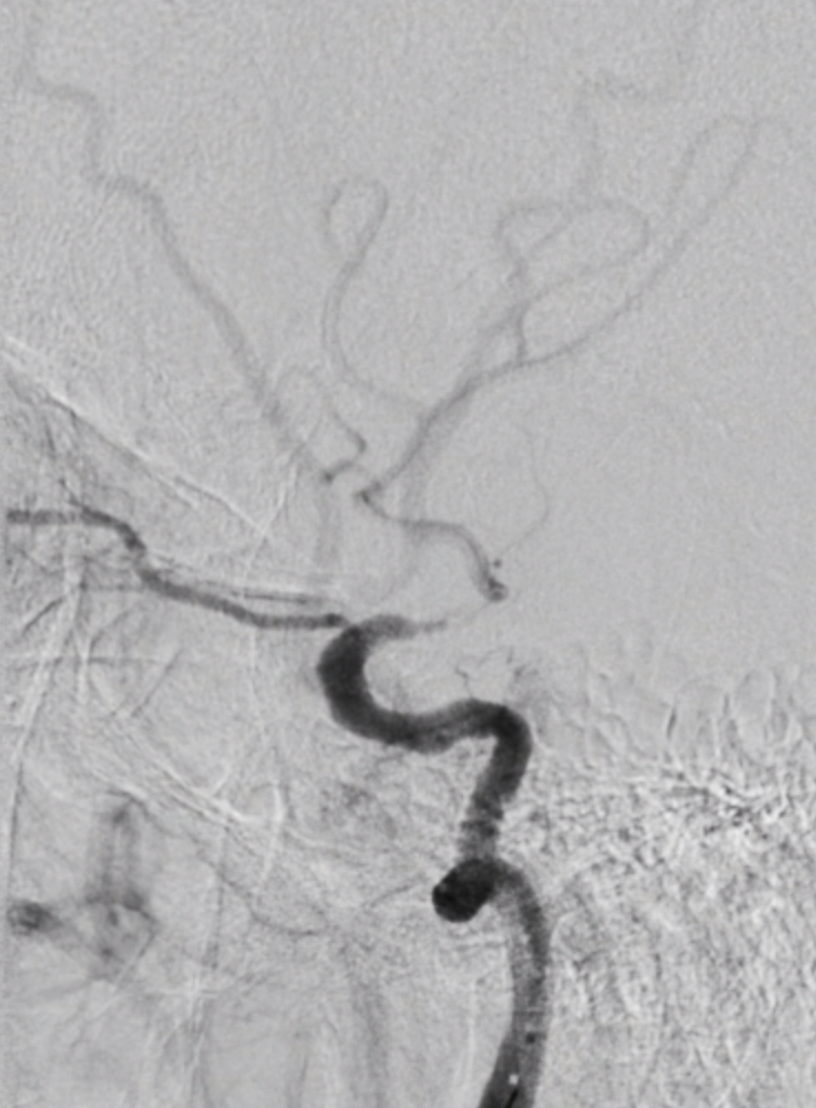

Tại bệnh viện, qua chụp DSA, bệnh nhân được chẩn đoán bị tổn thương hẹp khít cuối động mạch cảnh. Ông P. được can thiệp nong bóng và đặt stent nội sọ, dùng các thuốc hạ mỡ máu, thuốc dự phòng huyết khối… Sau can thiệp, sức cơ dần phục hồi.

Sau khi kết thúc 75 phút can thiệp mạch não cấp cứu, hút huyết khối và nong bóng mạch não, bệnh nhân tỉnh, sức cơ phục hồi, còn nói ú ớ.

11h40 cùng ngày, việc can thiệp nội mạch cho bệnh nhân được triển khai và kết thúc trong 50 phút. Hậu can thiệp, bệnh nhân tỉnh, sức cơ hồi phục 5/5. Một tháng sau, bệnh nhân tiếp tục được đặt stent can thiệp hẹp động mạch cảnh và sức khỏe dần phục hồi.